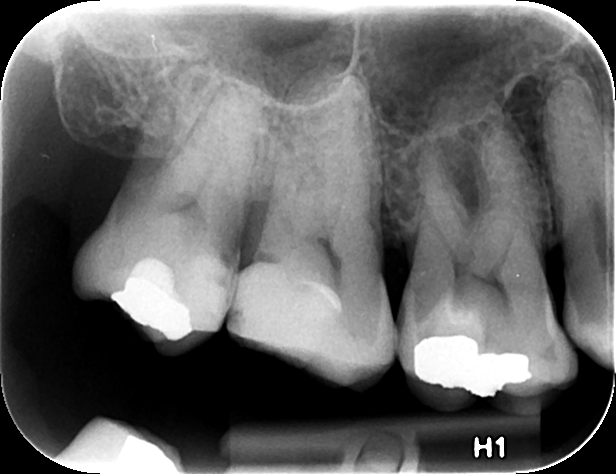

Η οπισθοφατνιακή ακτινογραφία λαμβάνεται με την τοποθέτηση του ακτινογραφικού πλακιδίου εσωτερικά των δοντιών (προς την πλευρά της γλώσσας ή του ουρανίσκου) και παράλληλα με αυτά. Χρησιμοποιείται ειδικός συγκρατητήρας του φιλμ, τον οποίο δαγκώνει ο εξεταζόμενος. Με αυτή απεικονίζονται ένα ή περισσότερα δόντια (τόσο η μύλη, όσο και η ρίζα αυτών), καθώς και τμήμα του φατνιακού οστού που περιβάλλει τις ρίζες των δοντιών. Αποτελεί την πιο απλή οδοντιατρική ακτινογραφική απεικόνιση. Χρησιμοποιούνται τρία μεγέθη φιλμ ή πλακιδίου ανάλογα με την περιοχή που θέλουμε να απεικονιστεί, το μέγεθος του στόματος του εξεταζόμενου και την ηλικία του. Η λήψη της είναι γρήγορη (διαρκεί λίγα δευτερόλεπτα) και ανώδυνη.

Η οπισθοφατνιακή ακτινογραφία μεταξύ άλλων μας επιτρέπει:

• την ανίχνευση οδοντικών τερηδόνων, τον καθορισμό της έκτασης και του βάθους τους και της σχέσης τους με τον πολφό του δοντιού

• τη μελέτη των ριζών των δοντιών (αριθμός, μορφολογία και πιθανή κάμψη αυτών, ύπαρξη απορρόφησης ή κατάγματος)

• τη μελέτη του αριθμού, της μορφολογίας, του εύρους και της πορείας των ριζικών σωλήνων εντός των ριζών

• τη μελέτη των σκληρών ιστών του περιοδοντίου, δηλαδή του φατνιακού οστού που περιβάλλει και στηρίζει το δόντι και του περιοδοντικού συνδέσμου. Σε περίπτωση περιοδοντικής νόσου, καθορίζεται η εντόπιση, ο βαθμός και η φύση (οριζόντια, γωνιώδης) της απορρόφησης του φατνιακού οστού

• τη μελέτη του φατνιακού οστού της περιακρορριζικής περιοχής του δοντιού για ύπαρξη παθολογικών εξεργασιών (απόστημα, κοκκίωμα, κύστη κ.λ.π.)

• την ανίχνευση κατάγματος των δοντιών.